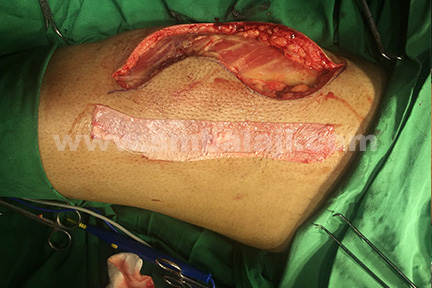

Tensor fascia lata graft obtained from the vastus lateralis muscle